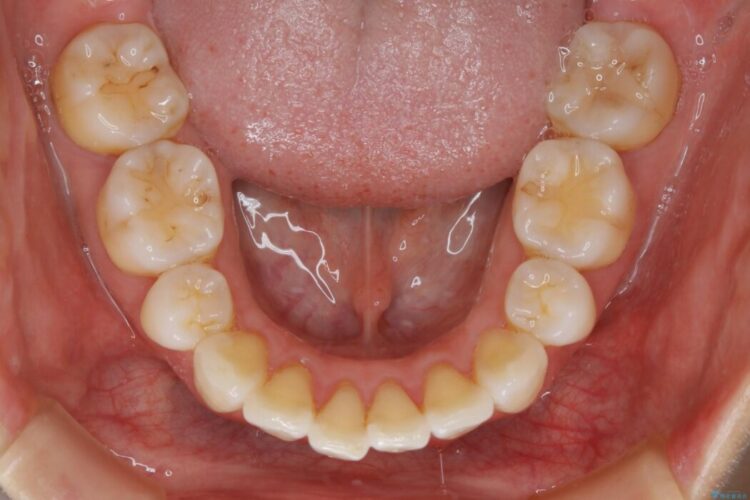

抜歯矯正後の上の前歯の後戻りが気になるとご来院された患者様です。

歯と歯の間を削るのと、歯列のU字型のアーチを僅かに外側に広げる事でスペースを作り、前歯の角度の改善をしました。

保定装置は、マウスピースと前歯の裏側を細いワイヤーで固定(ボンディングリテーナー)を併用していただいてます。